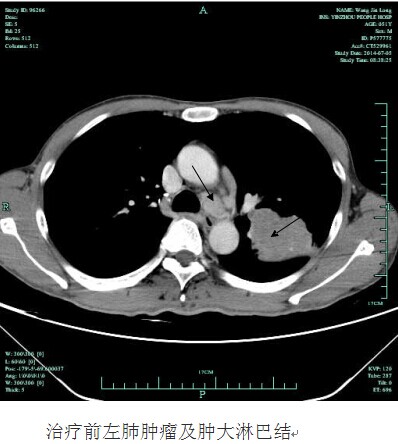

今年50岁家在我市江北区的王师傅,一个月前连续1周突然莫名发热,自行服了很多药都未见好转。由于体温一直徘徊在38.0左右,老王来到我院呼吸科就诊,门诊检查后,发现王师傅血红蛋白明显偏低,考虑贫血,当即将他收治入院。患者入院后,经胸X片等各项常规检查发现,王师傅左侧肺部有一巨大的阴影。进一步的胸部CT提示:首先考虑恶性肿瘤,且肿瘤巨大,有7X8CM大小,肿瘤内部已经发生溃烂坏死,同时远处的淋巴结已经转移。随后的肺活检证实王师傅得了肺腺癌。因为肿瘤已经晚期,错过了手术的机会,王师傅体质又偏弱,恐怕无法耐受化疗,全家人天天以泪洗面,王师傅更是已到精神崩溃边缘。针对患者的严重病情,为挽救其生命,呼吸科学科带头人俞万钧副院长和彭卫东主任,经多次组织科室讨论治疗方案,同时对患者病例通过远程网络会诊,和浙江省肿瘤医院的权威专家制订了放射性粒子碘125置入肿瘤的姑息治疗方案。手术在局麻下进行,其方法是首先在CT定位下确定粒子置入的位置,进定位针,深入肿瘤内部,沿定位针放置放射性粒子。手术非常顺利,术中王师傅一直保持清醒状态,术后3天,王师傅就出院了。昨日王师傅来我院复诊,除早已没有发热症状外,整个人精神状态非常好,和常人无异,胸部CT复查发现左肺的肿瘤已经缩小近一半,更为不可思议的是,王师傅左胸肿大转移的淋巴结也变小了。据悉,接下去呼吸科将为王师傅制定下一步诊疗计划,以抑制肿瘤的再次增长。